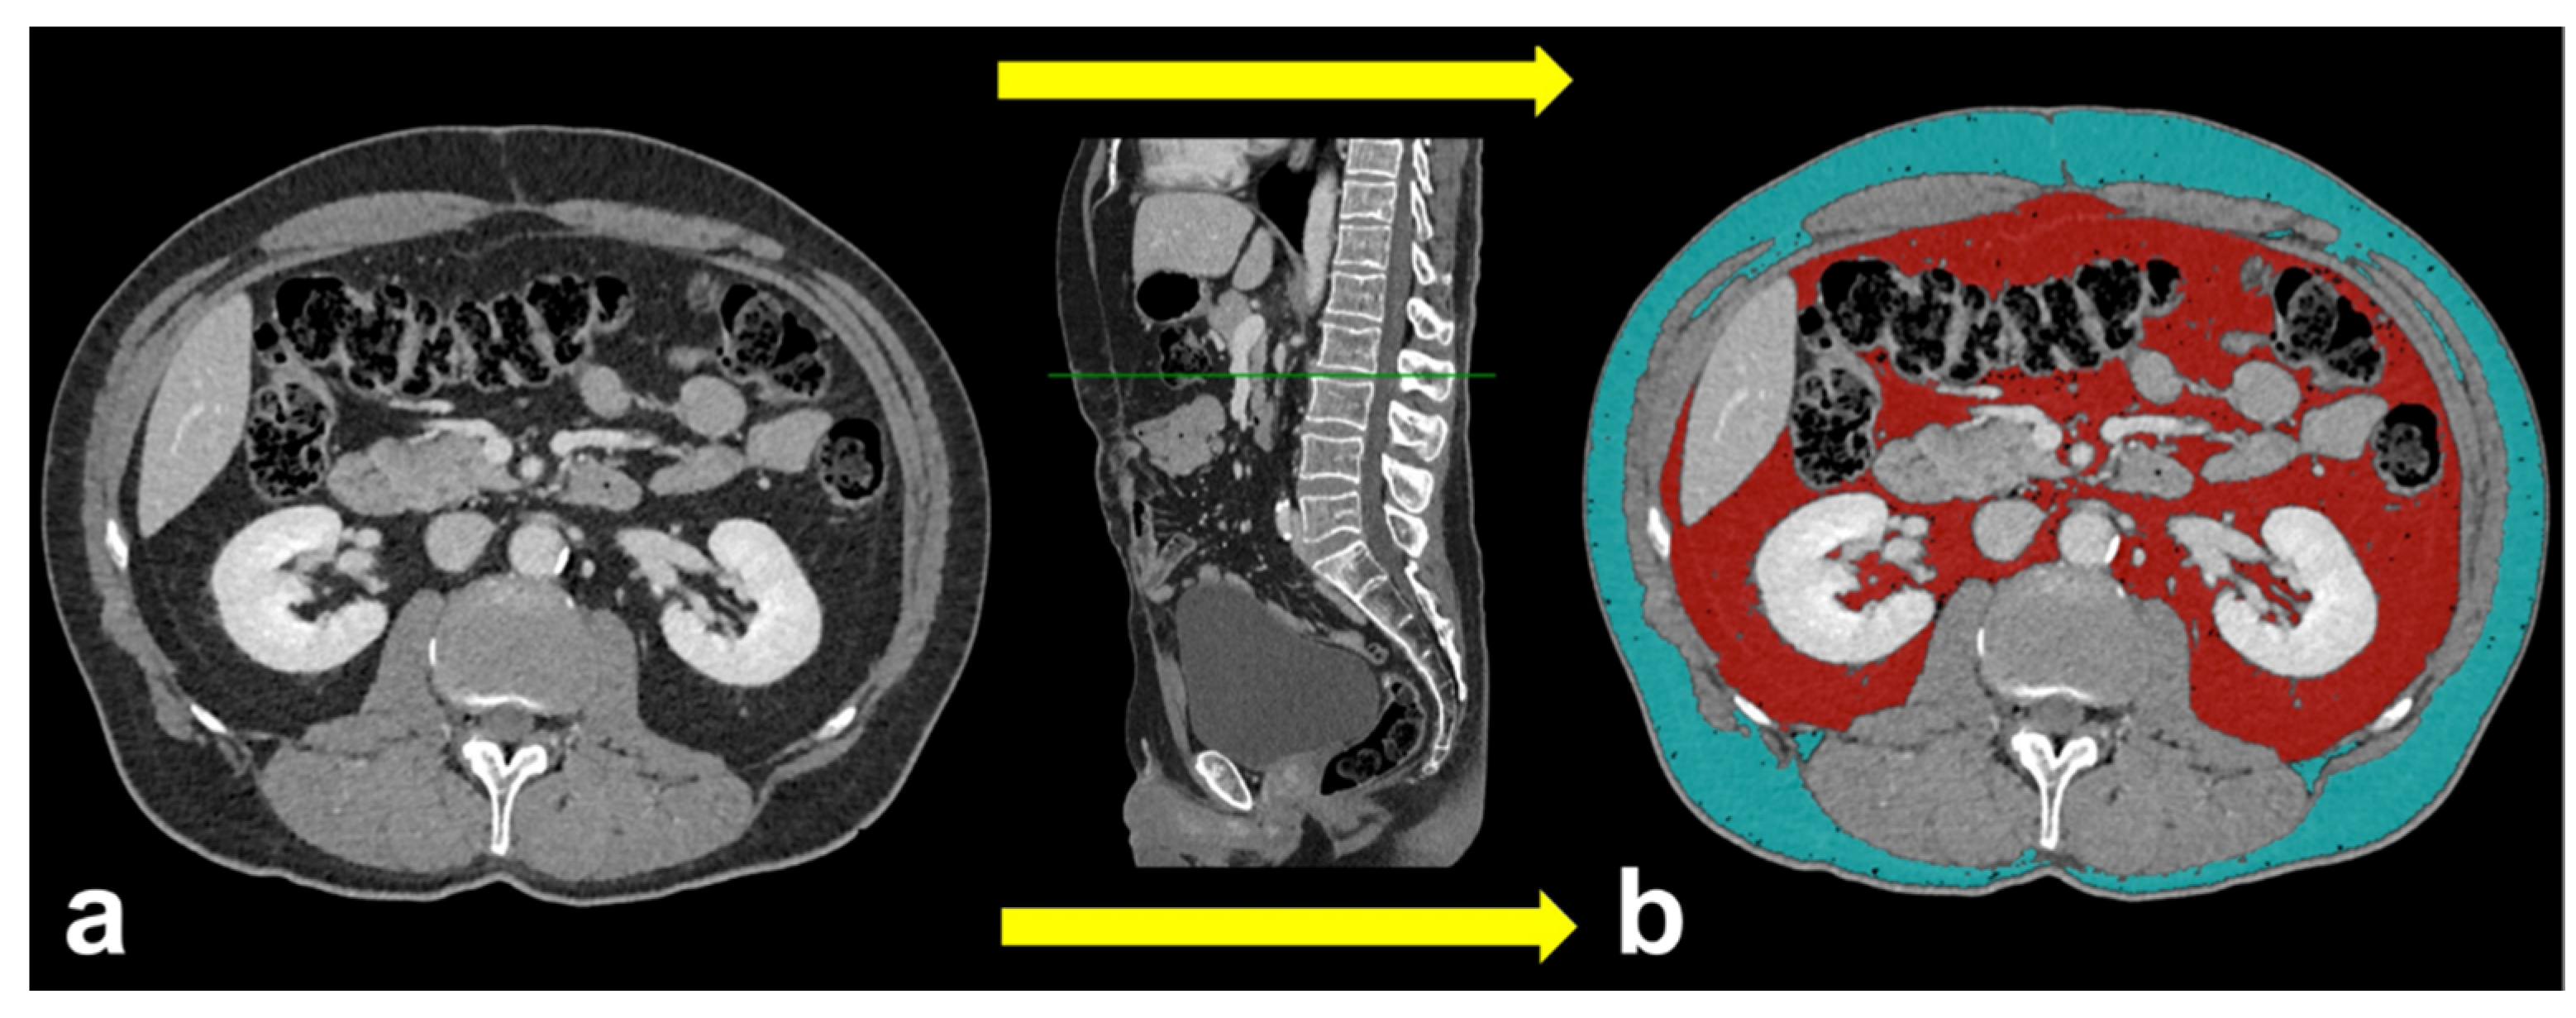

All patients underwent CT examination. For the evaluation of collateral vessels and quantification of adipose tissue we used CT images obtained after intravenous administration of an iodine-based contrast medium. Horos v.4.0.0 RC2 software was used for the quantification of TAT, VAT and SAT, by means of a semi-automatic function that allowed us to detect the attenuation values of adipose tissue (i.e., about −100 Hounsfield Unit). The slice chosen for the measurements of areas (cm2) was located 3 cm above the lower margin of L3, according to a previously described technique (Figure 2) [18]. All the regions of interest (ROIs) were drawn by consensus of two radiologists (F.G., 5 years of experience; C.A.M., 9 years of experience), blinded to clinical data.

Figure 2.

Axial CT images showing a single slice located 3 cm above the lower margin of L3 without ROIs (a) and the same slice with superimposed colored ROIs of VAT area (red ROI) and of SAT area (cyan ROI) (b). The sagittal plane, depicted in the middle, has been used as a reference to drive the correct ROI drawing for each subject.